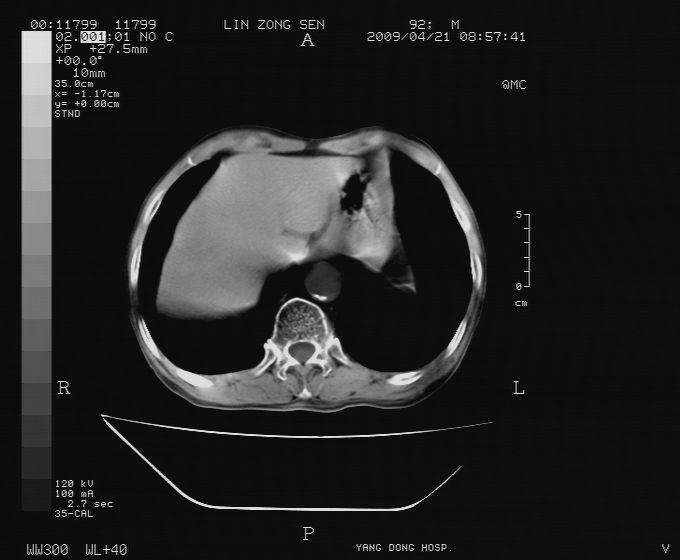

以下是引用卜一在2009-4-22 4:08:00的发言:[br]右肾积水伴输尿管上段积水!左侧肾多发囊肿!左侧腹壁软组织增厚,层次模糊,内密度较高—不排除血管瘤伴出血!